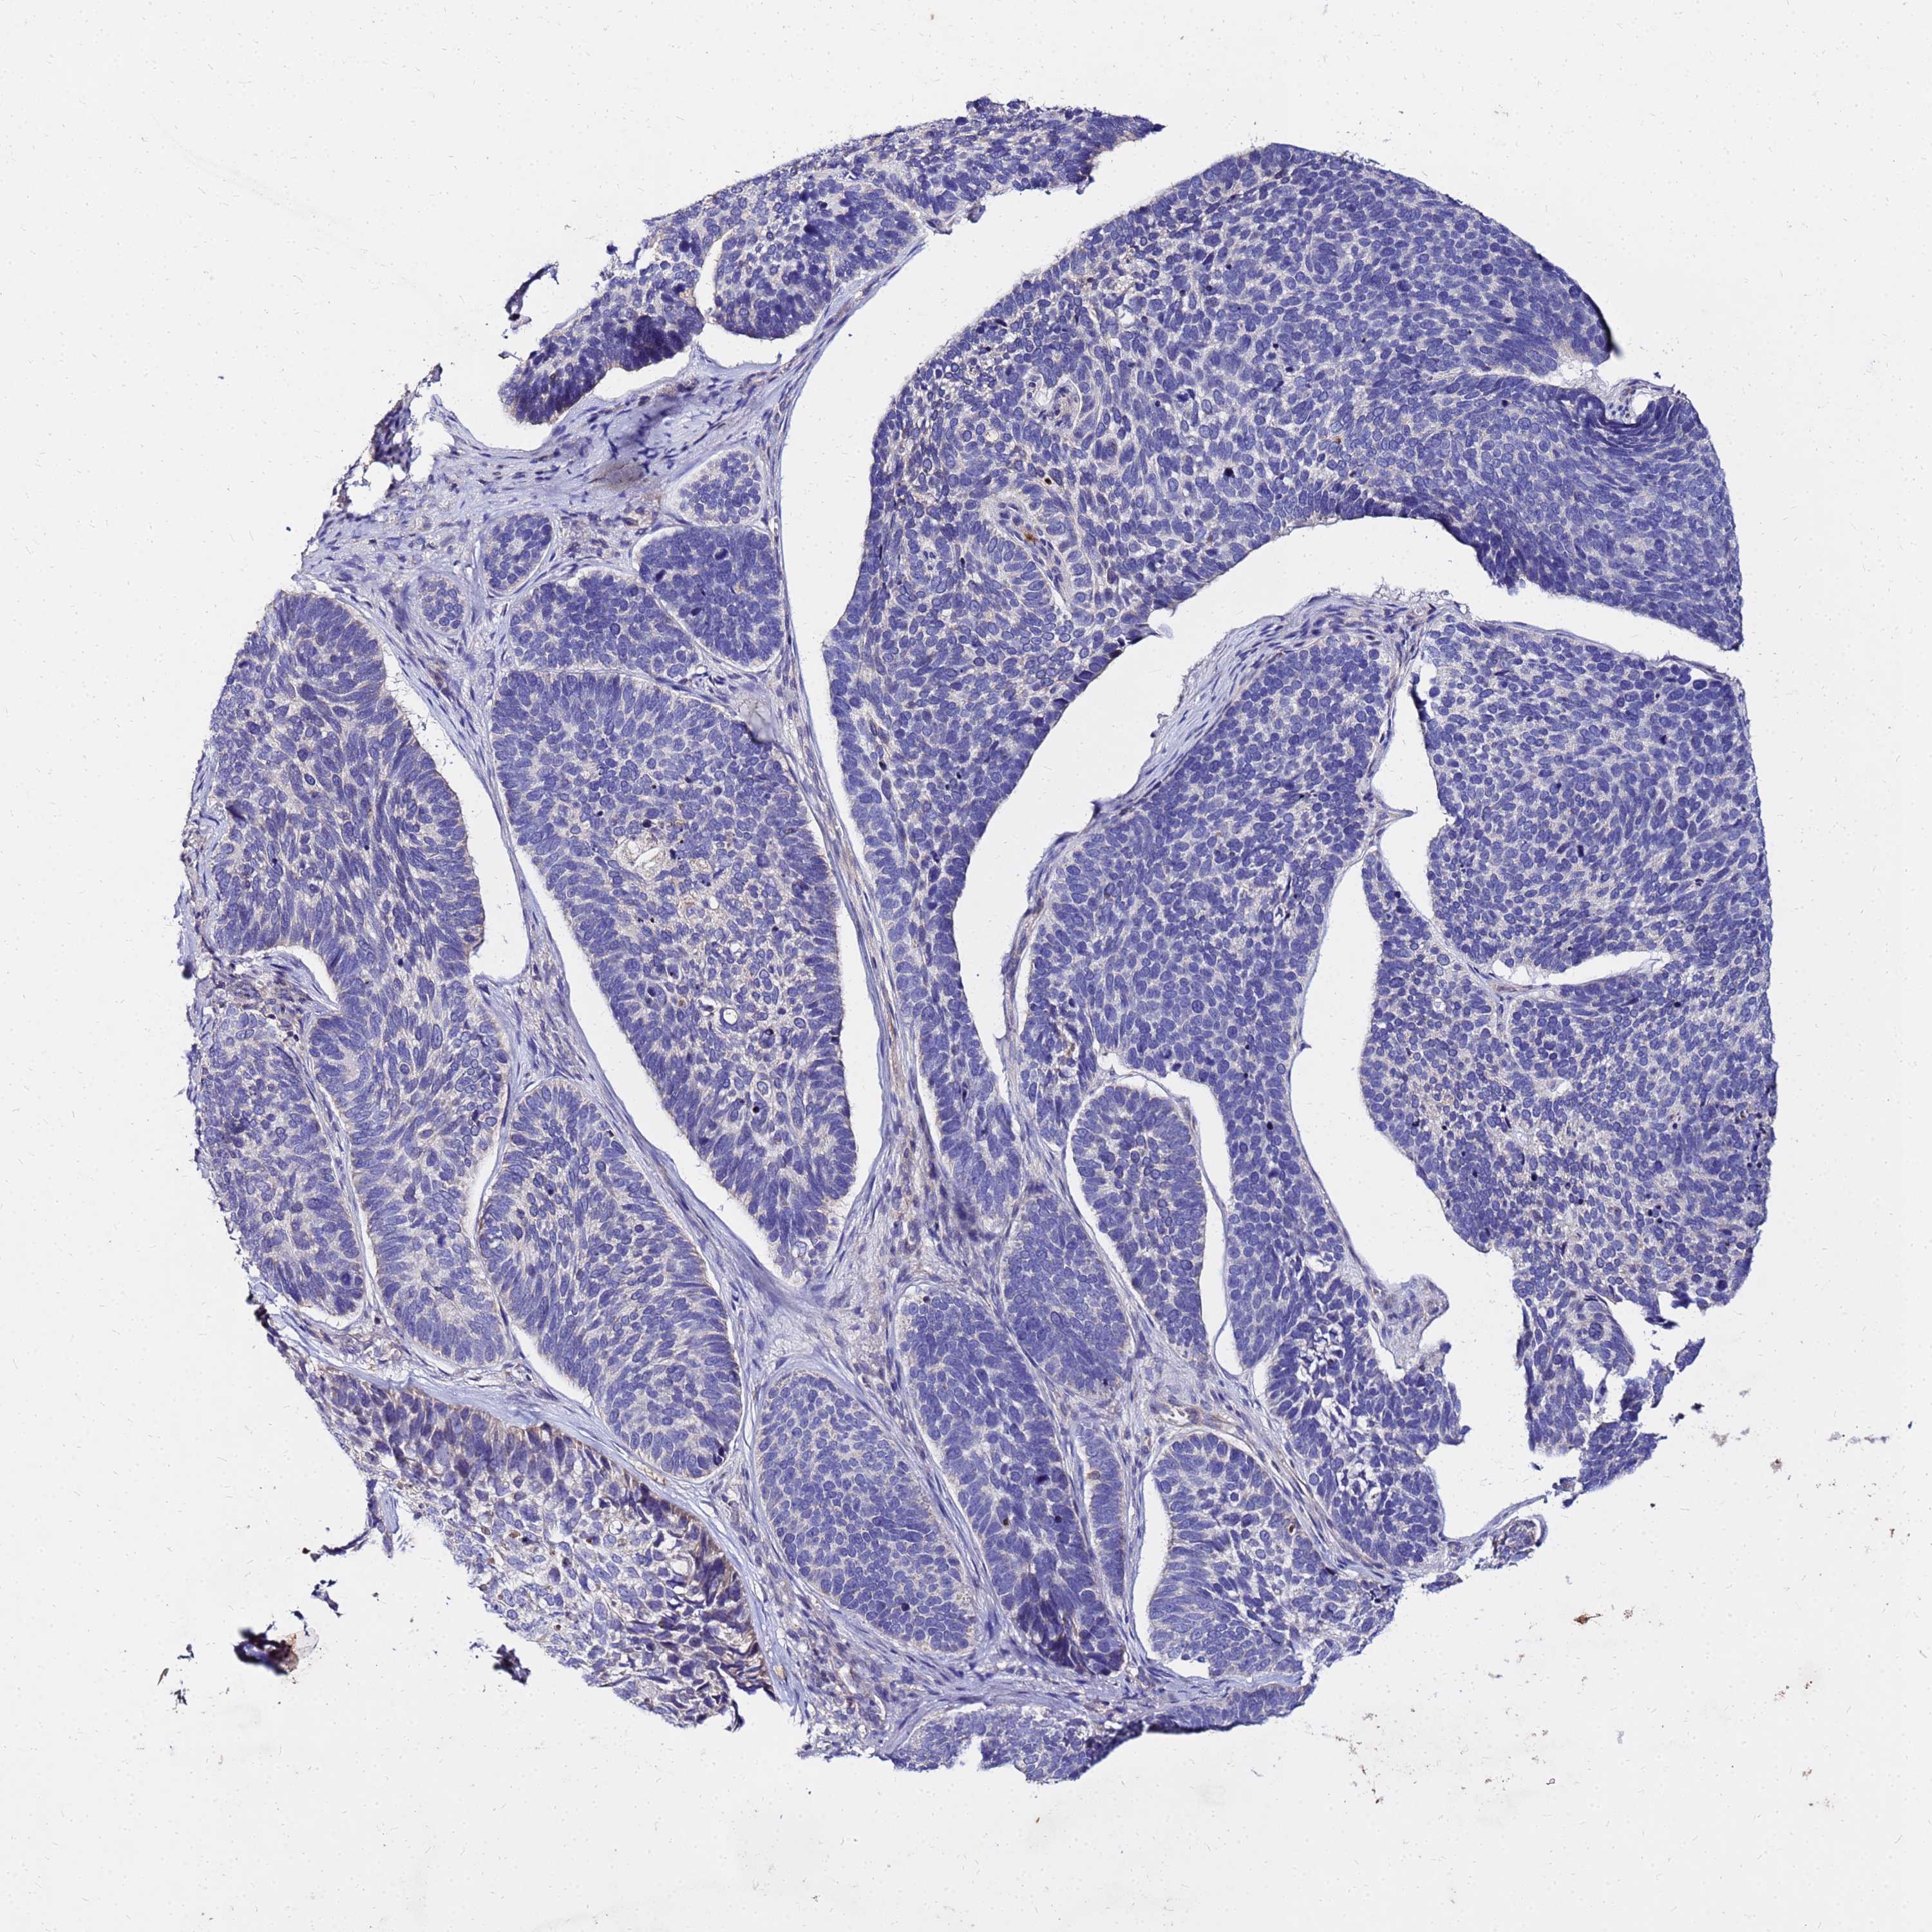

SKIN CANCER - Protein expressioni

A mouse-over function shows sample information and annotation data. Click on an image to view it in a full screen mode. Samples can be filtered based on level of antibody staining by selecting one or several of the following categories: high, medium, low and not detected. The assay and annotation is described here.

Antibody stainingi

Antibody staining in the annotated cell types in the current human tissue is reported as not detected, low, medium, or high, based on conventional immunohistochemistry profiling in selected tissues. This score is based on the combination of the staining intensity and fraction of stained cells.

Each image is clickable and will lead to virtual microscopy that enables deeper exploration of all samples and also displays staining intensity scores, fraction scores and subcellular localization as well as patient and tissue information for each sample.

Antibody HPA044618

Antibody HPA062014

Basal cell carcinoma

Squamous cell carcinoma, NOS

Squamous cell carcinoma, metastatic, NOS

BCC, high aggressive